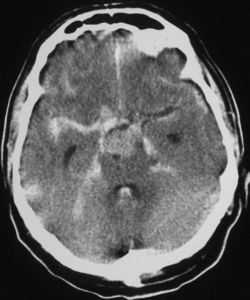

| CT scan of the brain showing subarachnoid hemorrhage as a white area in the center | |

نزف تحت العنكبوتية Subarachnoid hemorrhage (SAH)، أو subarachnoid haemorrhage، هو نزيف داخل الحيز تحت العنكبوتية subarachnoid space المحيط بالمخ، وهي المنطقة بين الغشاء العنكبوني arachnoid membrane والأم الحنون pia mater. فيه يحدث النزف ضمن الطبقة السحائية العنكبوتية. وأكثر الأسباب شيوعاً هو رضوض الدماغ، أما حالات النزف غير الرَّضِّيّ فتنتج عادة من انفجار أم دم aneurysm (وهي توسع كيسي غير طبيعي في شريان أو أكثر). ومن الأسباب الأخرى التشوهات الشريانية الوريدية، والتهاب الأوعية، وتسلخ الشرايين، واعتلالات التخثر، وخثار الجيوب الوريدية، وفقر الدم المنجلي، وتمزق شريان سطحي صغير. ويبقى السبب مجهولاً في نحو 14ـ22% من الحالات. وفيما يأتي نبذة عن النزف تحت العنكبوتية الناتج من أمهات الدم لكونه الأهم بينها.[1]

يعتمد بصفة رئيسة على تصوير الدماغ، ومن أكثر طرق التصوير استعمالاً التصوير الطبقي المحوري (الشكل3)، وبدرجة أقل المرنان المغنطيسي. وجدير بالذكر أن تصوير الدماغ قد يخفق في إظهار النزف في نحو 5% من المرضى، وفي هذه الحالة يمكن اللجوء إلى استقصاء آخر هو البزل القطني للسائل الدماغي الشوكي. وتظهر دراسة السائل وجود أعداد كبيرة من الكريات الحمر، مما يثبت حدوث النزف.